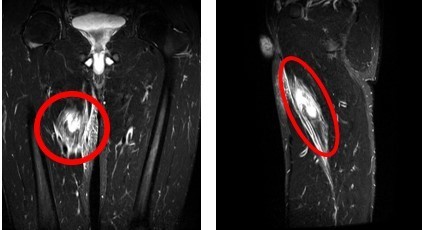

画像所見:MRI検査で内転筋の損傷を確認しました。(で囲んだ部分)

正面から見た場合)      (横から見た場合)

診断:『内転筋の肉離れ(Ⅱ度)』  スポーツ復帰目安(6週~8週間)